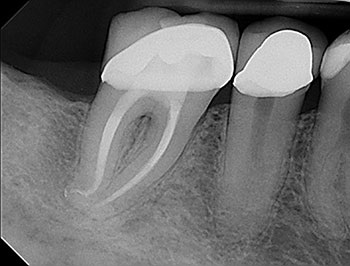

The patient returned in three months, when resolution of symptoms, healing of the deep probing defect and bone regeneration were confirmed. The tooth was obturated, and a foundational restoration was placed before the rubber dam was removed. Fourteen years of follow-up confirmed long-term periradicular health. The amount of appreciation and gratitude that this patient expressed reminds us that each individual tooth demands our best efforts.

Fig. 3: Recall PA.